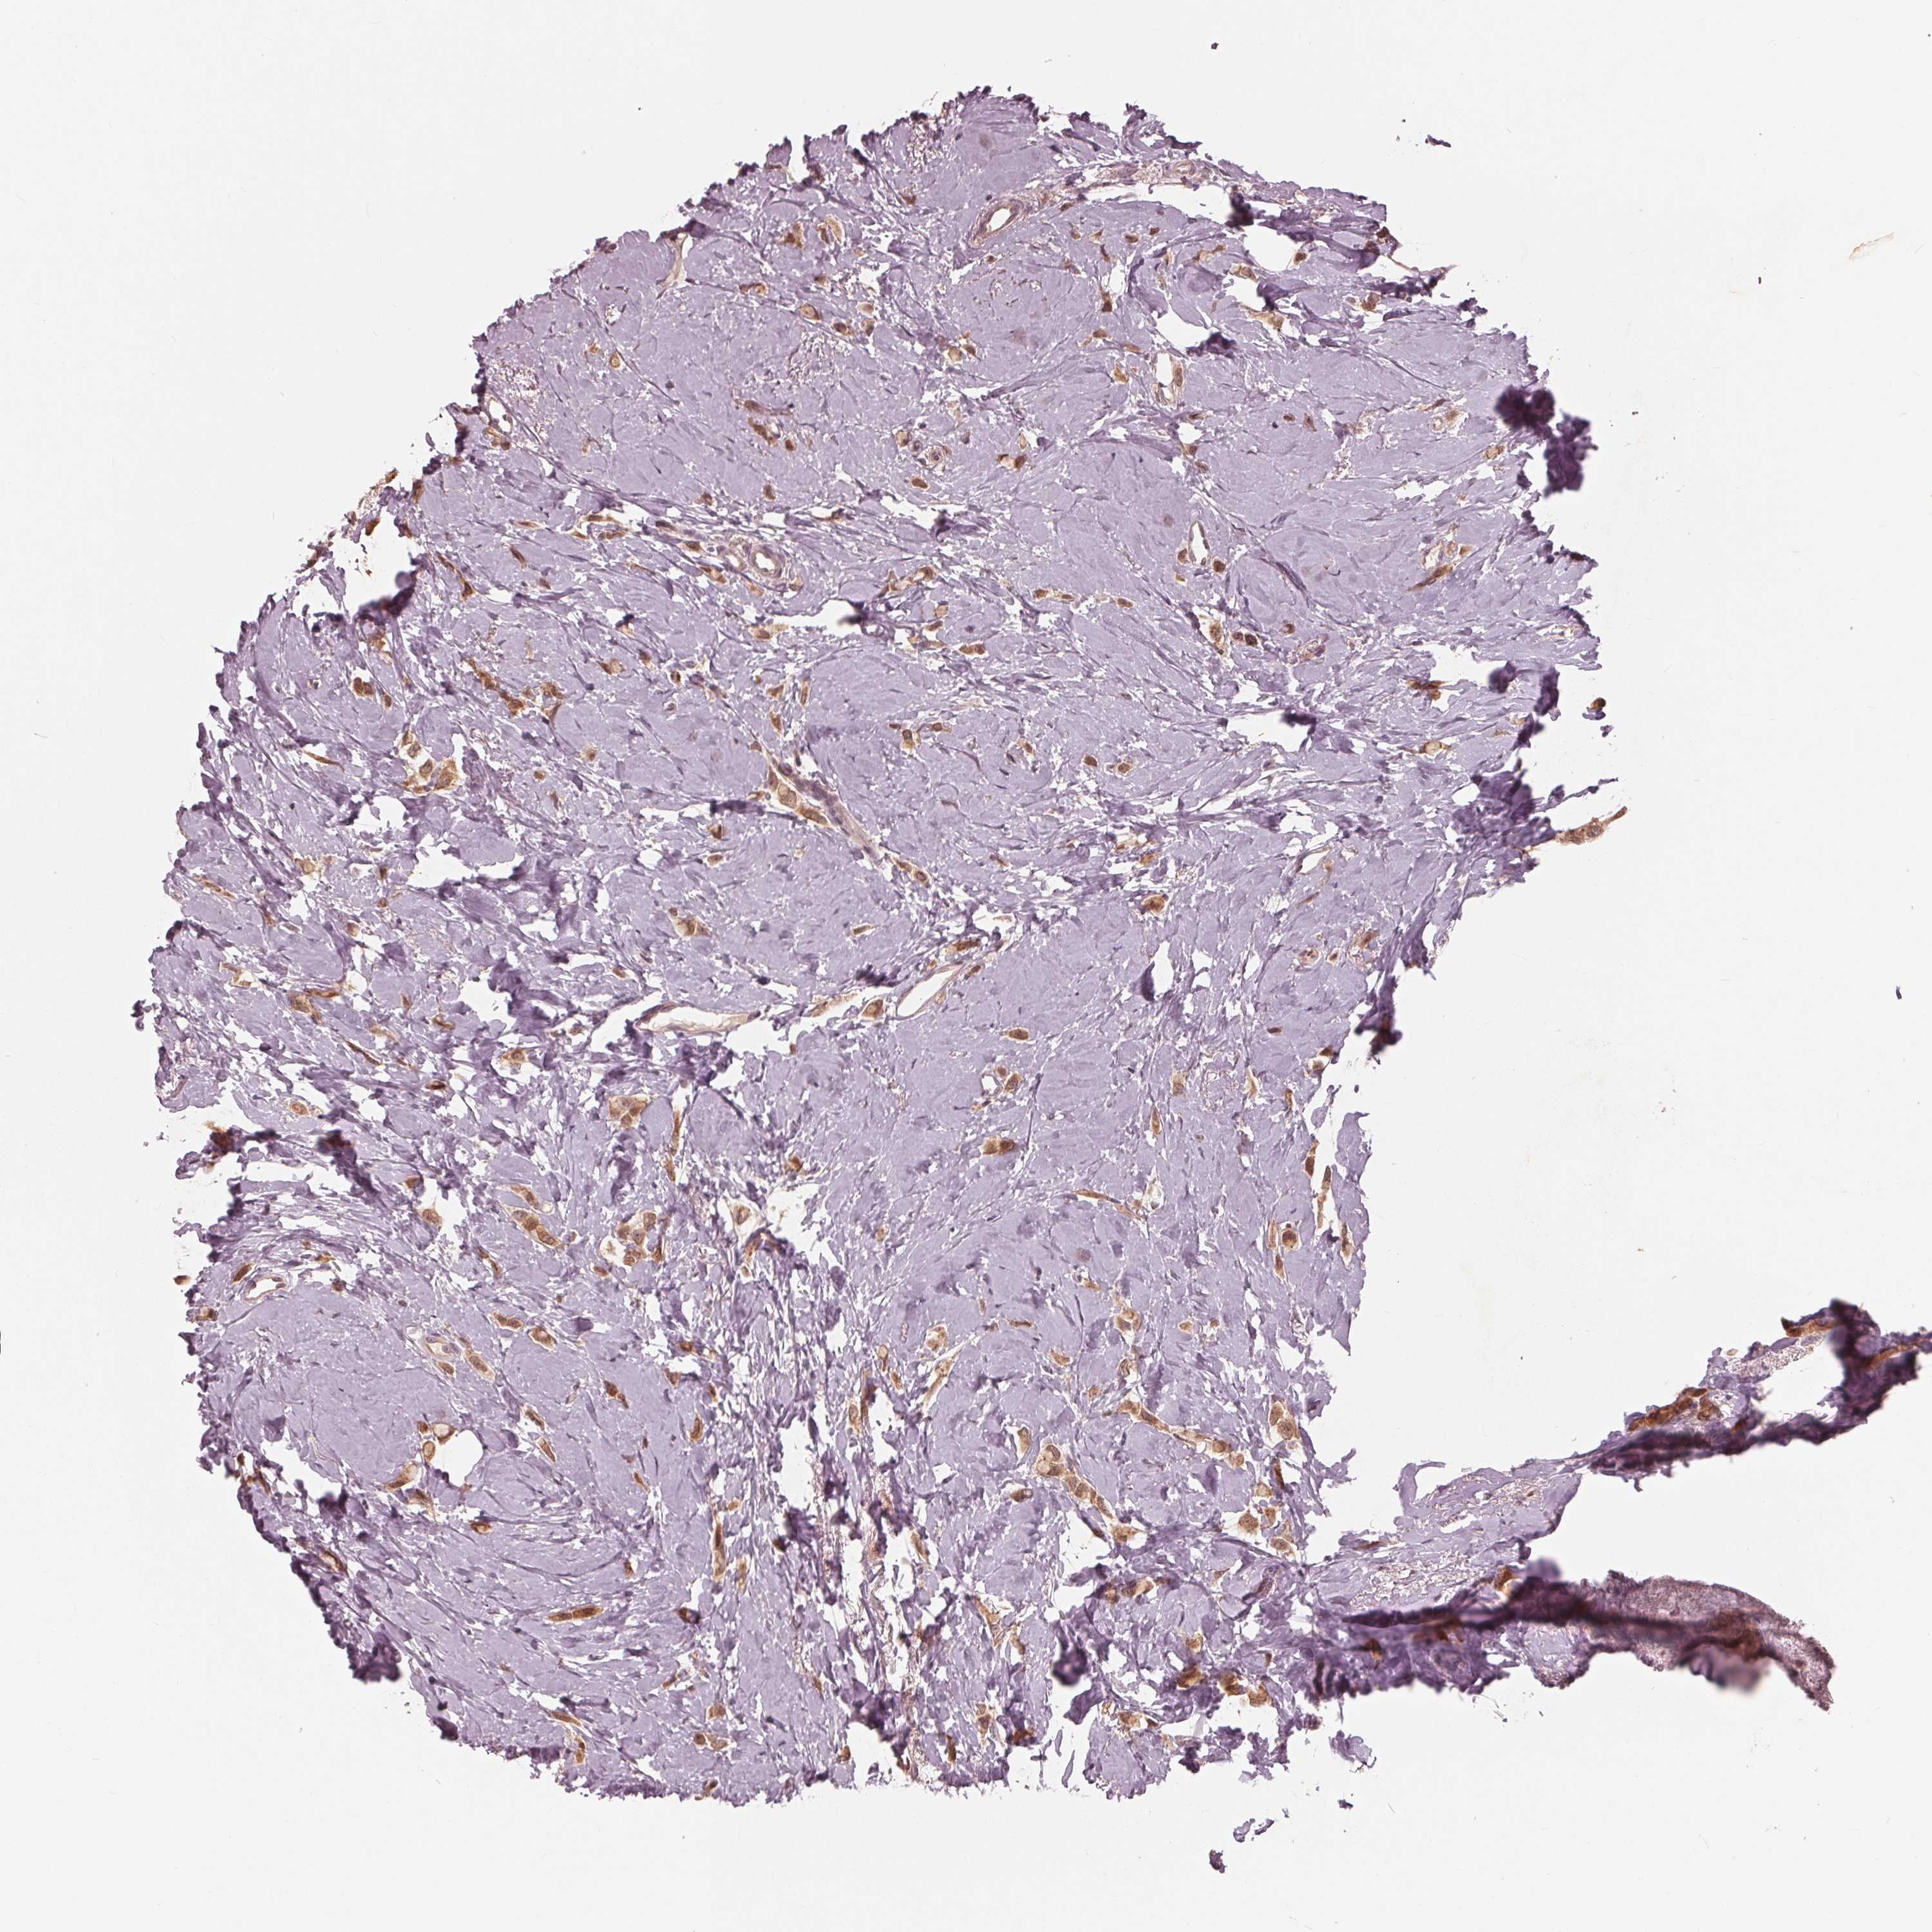

CANCER BREAST CANCER Show tissue menu

BRCA TCGA BRCA VALIDATION PROTEIN EXPRESSION

ANTIBODIES

AND

VALIDATION